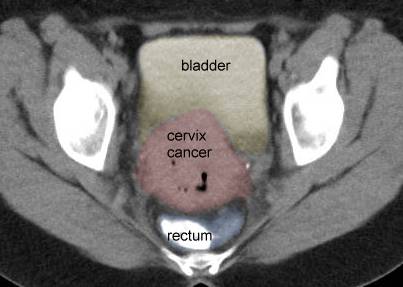

- CT

of early and advanced cervix cancer